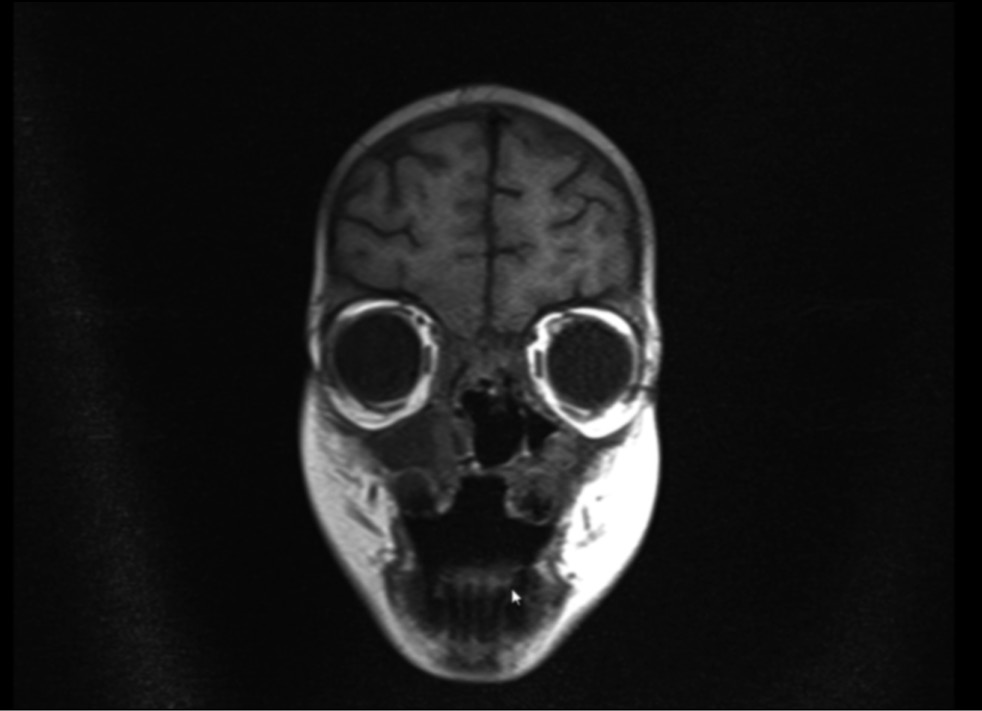

Рентгеновскую компьютерную томографию проводили в динамике на 36, 47, 63-й дни госпитализации. РКТ орбит и придаточных пазух носа выявила признаки множественных обширных очагов деструкции медиальных стенок орбит, костей носовой полости, твёрдого нёба, альвеолярных отростков верхнечелюстной кости, дефект мягкого нёба (рис. 4, 5). С помощью магнитно-резонансной томографии орбит, придаточных пазух носа, головного мозга на 63-й день госпитализации обнаружены признаки множественных обширных очагов деструкции медиальных стенок орбит, костей носовой полости, твёрдого нёба, альвеолярных отростков верхнечелюстной кости, дефект мягкого нёба (рис. 6, 7).

Рис. 6. Магнитно-резонансная томография орбит, придаточных пазух носа, головного мозга на 63-й день госпитализации в коронарной проекции.

Fig. 6. Magnetic resonance imaging of the orbits, paranasal sinuses, and brain in the coronary projection on the day 63 of hospitalization.

Рис. 7. Магнитно-резонансная томография орбит, придаточных пазух носа, головного мозга на 63-й день госпитализации в аксиальной проекции.

Fig. 7. Magnetic resonance imaging of the orbits, paranasal sinuses, and brain in the axial projection on day 63 of hospitalization.